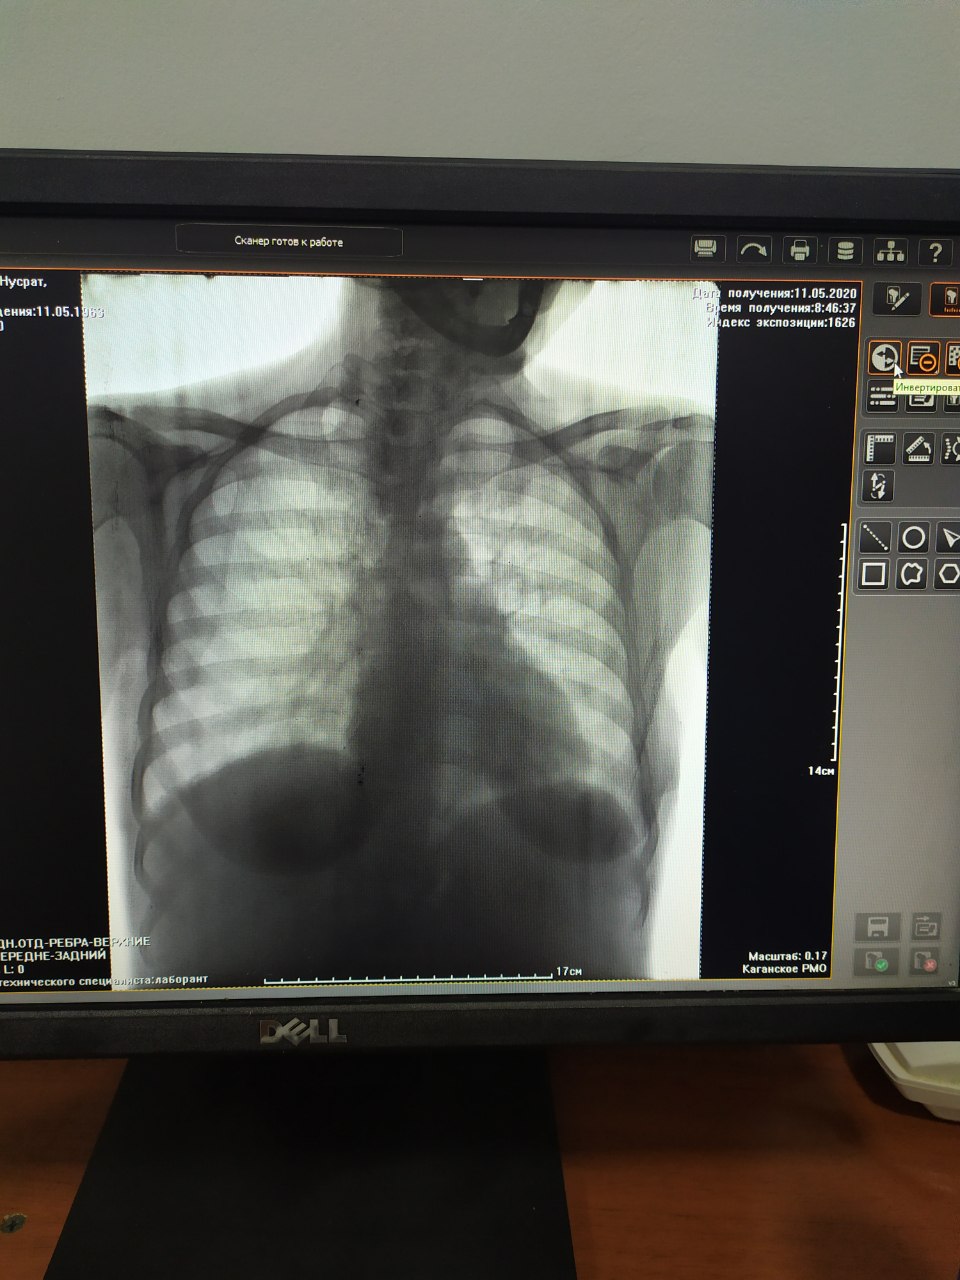

У корня справа не очень и слева  на 4 ребро вроде как наслаивается что-то

Или норма)

Во время снятия вдохнула что ли, повторно снимайте !

Чёткость неточно видно!

Доброго дня, пацієнт звернувся із скаргами на болі в ділянці 10-12 ребер, анамнестично : падіння в маршрутці.

С какого бока?

И вообще для ребер надо делать ещё косую, на прямой можно напропускать